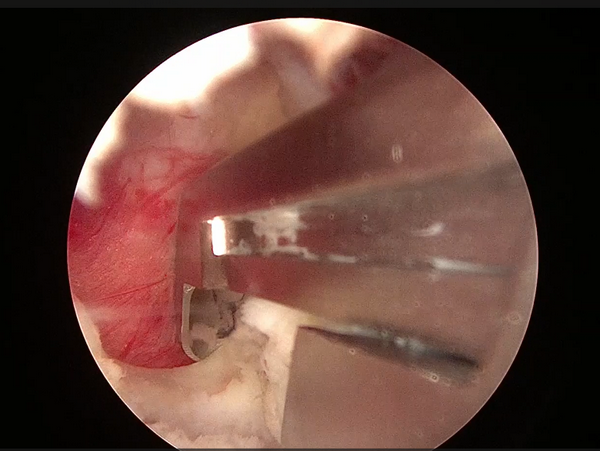

髓核摘除前后对比

患者接受手术治疗,术中仅通过两个长约0.5cm及1cm的手术切口,置入脊柱内镜及操作器械,逐步扩大“狭窄的椎管”并顺利摘除“脱出的椎间盘组织”,解除神经受压情况。

3.切除黄韧带

4.显露椎间盘